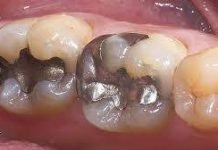

Affordable All-on-4 Dental Implants in Brisbane: Your Comprehensive Guide

Introduction: Are you considering All-on-4 dental implants but worried about the cost? Sandgate Bayside Dental is here to make this transformative procedure accessible to...